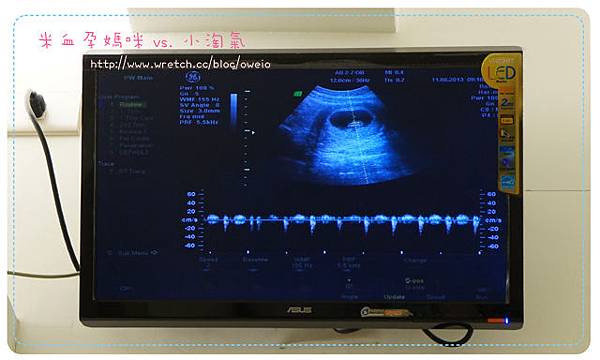

一樣也聽了小淘氣的心跳

我覺得這次的心跳聲跟上次的不太一樣耶~沒有第一次那麼的宇宙無敵快速

但還是很興奮,因為知道小淘氣還是好好的乖乖的在媽咪肚子裡快活![]()

![]()

小淘氣心跳聲